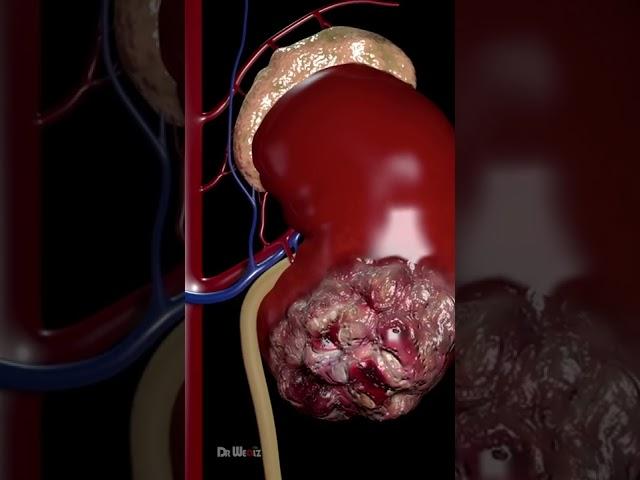

Signs & Symptoms of Kidney Cancer (Animation)